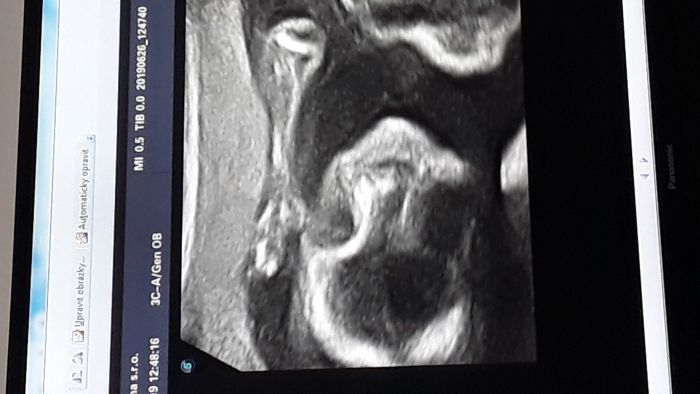

ja mam dnes po druhé kontrole v rámci 2. screeningu a vše v pořádku, dnes bylo srdíčko vidět okamžitě tak, jak pan doktor potřeboval, sám se smál, že dnes malá spolupracuje uplne vzorně

Blani, to nám se na první pokus nakrucovala moc pěkně, že máme spoustu pěkných fotek, ale bohužel to srdíčko neukázala ze všeh potřebných úhlů, tak jsme si to holt museli zopakovat

Nam srdicko taky moc nechtela ukazat, ale pak se podarilo, takze jsme znova nemuseli, a platili jste neco za ty fotky? Nam prave rekl ze nic platit nemusime, asi tim ze se moc nepovedly